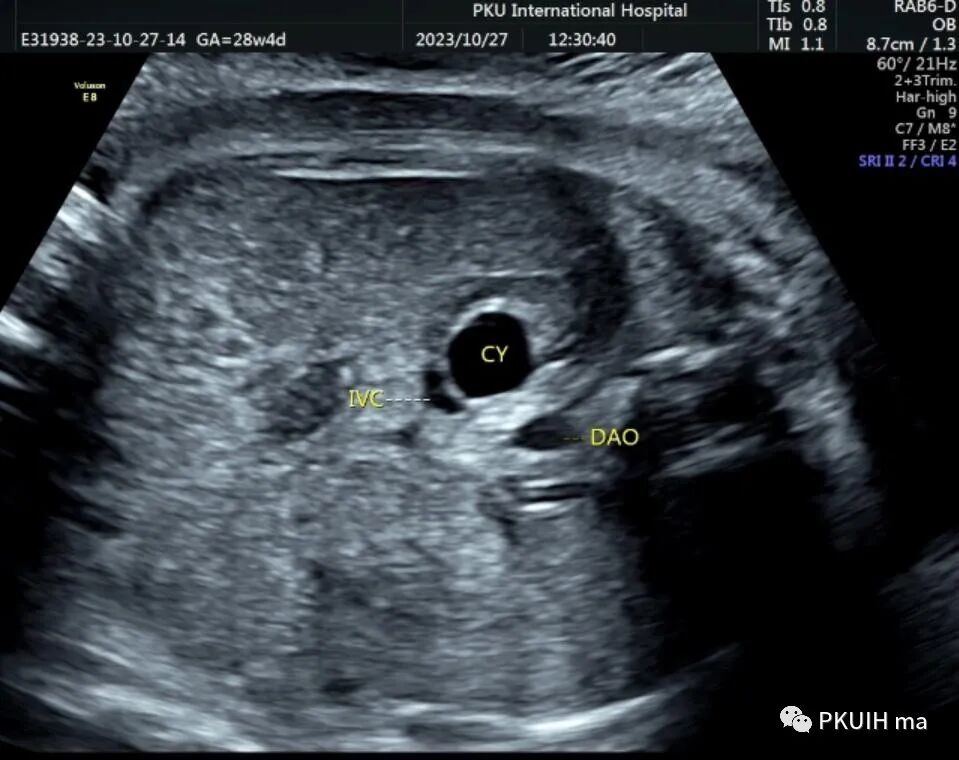

孕妇在之前超声检查中均未见异常,在28周常规超声筛查中发现右侧肾上腺区见一囊肿回声,大小约1.3x1.0cm。随访观察中发现囊肿逐渐增大,胎儿其他各项指标未见明显异常。目前仍在定期随访中

肾上腺出血可能是自发性的,但也有一些诱发因素,如: 抗凝血剂,预先存在的良性肾上腺囊肿,凝血功能缺陷,如因子 IX 或 X 缺乏,血管性血友病,低血小板计数,抗磷脂综合征,药物影响或肿瘤破裂。出血大部分是自限性的,自发性消退是常见的结果;然而一些病例报道与胃肠道疾病相关,因此在围产期密切监测是必要的。右肾上腺比左肾上腺更容易受到影响,临床上这几年发现的也几乎都是右侧。双侧出血可能与Beckwith-Wiedemann syndrom(BWS,贝克-威德曼综合征)有关。